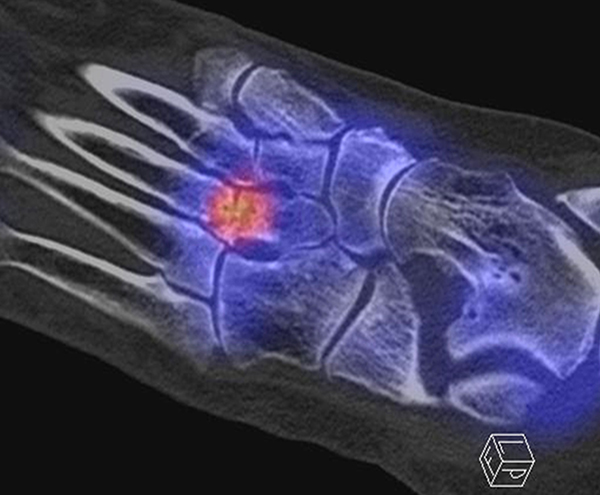

In Abbildung 3.4. ist ein typisches Beispiel für ein symptomatisches Os trigonum dargestellt.

Bei der Differenzialdiagnose von Impingement-Syndromen am Sprunggelenk kann das SPECT/CT den Ort der Symptome- verursachenden Stressreaktion darstellen 32. Eine typische Ursache für ein posteriores Impingement kann ein Os trigonum sein. Scherkräfte im Bereich der Synchondrose eines Os trigonum lösen hypermetabole Stressreaktionen aus. Die Exzision des Os trigonum stellt eine erfolgreiche Therapie dar, sodass der Befund eines szintigraphisch aktivierten Os trigonum den Erfolg einer chirurgischen Therapie vorhersagen kann 3334.